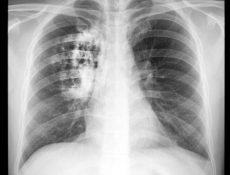

Tratamiento del cáncer de pulmón libre de quimioterapia

Johnson & Johnson continúa reafirmando su liderazgo en la lucha contra el cáncer al avanzar en soluciones innovadoras dirigidas al cáncer de pulmón, una de las principales causas de mortalidad por cáncer a nivel mundial. Apoyados por décadas de experiencia en investigación y desarrollo, la compañía transforma el panorama oncológico al brindar terapias avanzadas que ofrecen esperanza a pacientes y redefinen las expectativas de los tratamientos actuales. En el marco del Día Nacional del Cáncer de Pulmón, Johnson & Johnson se suma al llamado para fortalecer la conciencia sobre estaMás información…